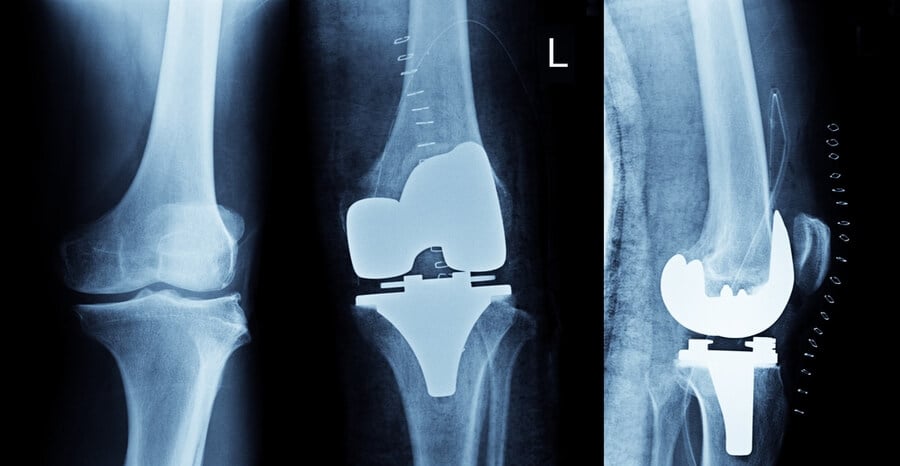

What not to do after knee replacement surgery

Recovering from knee replacement surgery requires careful adherence to post-operative guidelines to ensure successful healing and optimal outcomes.